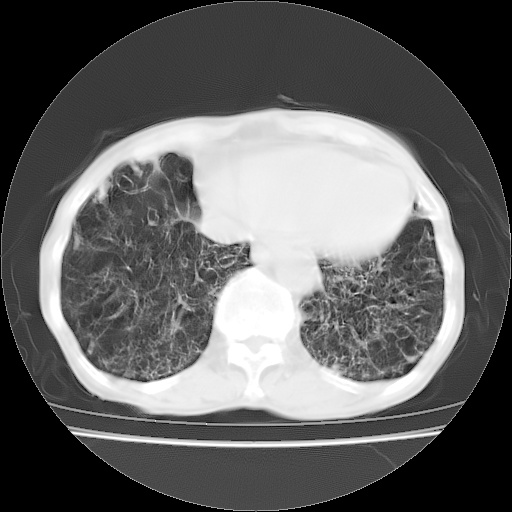

病人发热、气促就诊。原二周前已行ct扫描,当时诊断为双肺下叶、右肺中叶支气管扩张并感染,双肺上叶片状渗出性病变。今天复查胸部ct,双肺下叶支气管扩张并感染病灶较前明显吸收,但双肺上叶渗出性病变较范围较前明显增大。

现传今天ct图像给大家讨论。

双肺感染性病变,不排除机遇性肺炎。双下肺间质纤维化较明显。

双肺间质广泛纤维化,上叶炎症考虑特异性感染,例如念珠菌,克雷伯杆菌什么的,建议实验室检查。

双肺多发大片状、斑片状高密度渗出影,部分实变,考虑病毒性肺炎。